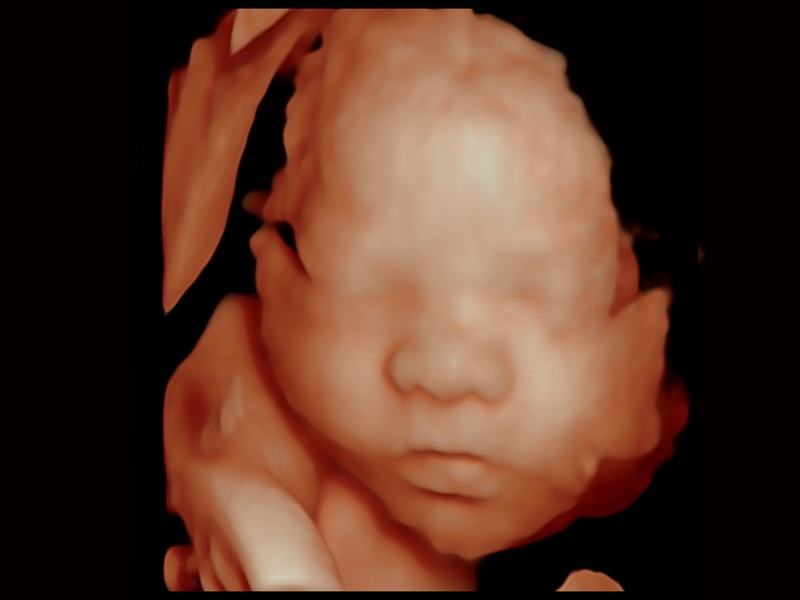

妇产科应用